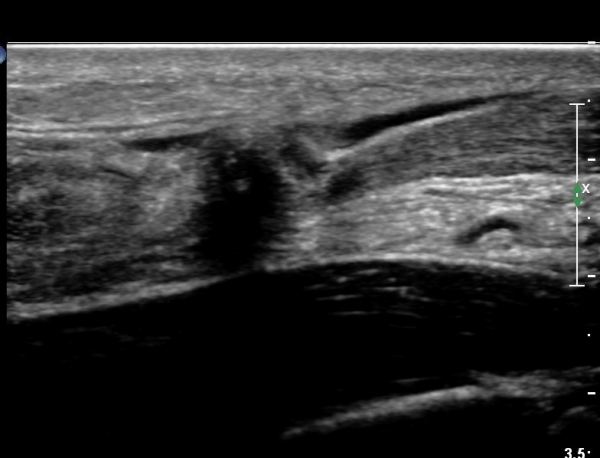

¾ÆÅ³·¹½º°Ç Ⱦ´Ü¸é°Ë»ç¿¡¼ ¾ÆÅ³·¹½º°Ç Àú¿¡ÄÚ ºÎÁ¾, ¿¬°á¼º ¼Ò½Ç, °ÇÁÖÀ§ ¼ö¾×Àú·ù ¼Ò°ßÀ» º¸ÀÓ(»çÁø 6, 7, 8).